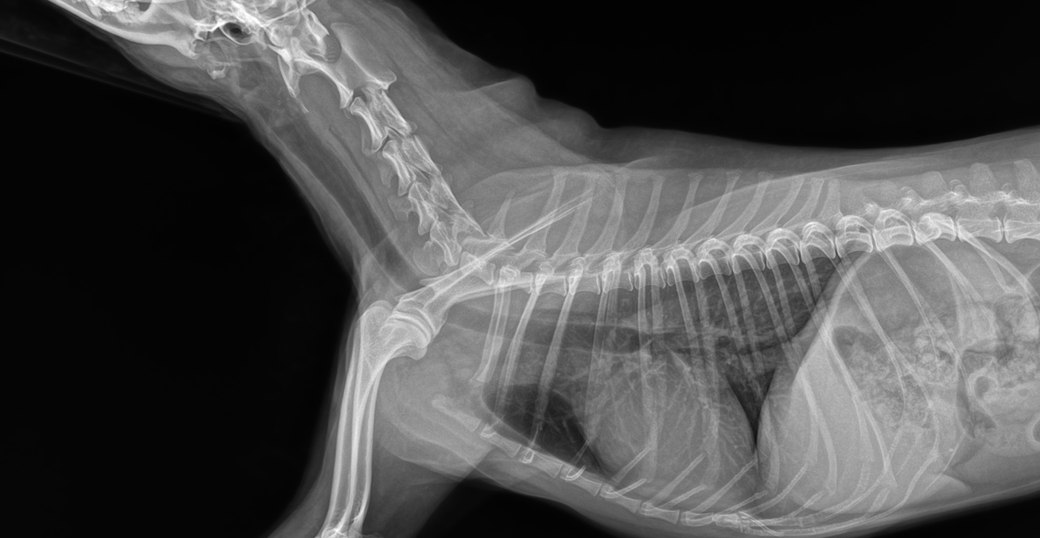

질문3. 해당 사진 2장으로 비인두 협착이 있다고 수의사분께서 그러셨습니다 증상이 심한편인가요?

3. 첫번째 사진에서 의심 딱 그정도만 할 뿐이지 진단적인 의미가 크지 않은 사진입니다. C-arm검사 및 CT검사가 필요합니다.